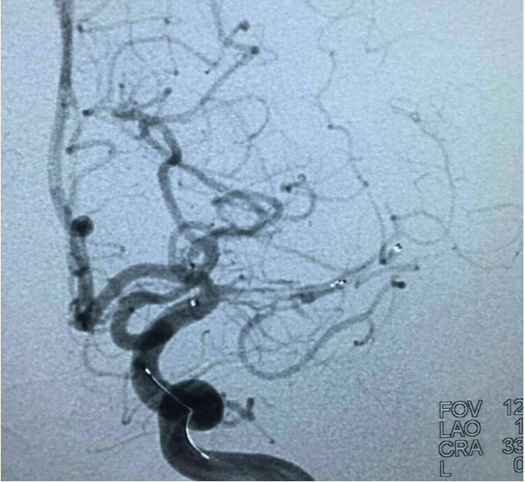

支架打开后:

最后造影:

术后第二天查看患者无不适,言语流利,四肢肌力5级,精神状态好转。继续双抗治疗。